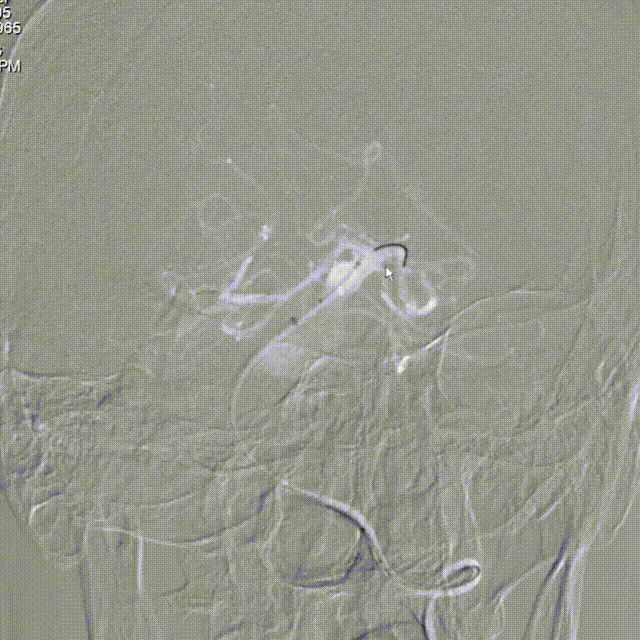

Lattice完全释放:

完全释放支架解脱。

造影显示整体打开贴壁良好。